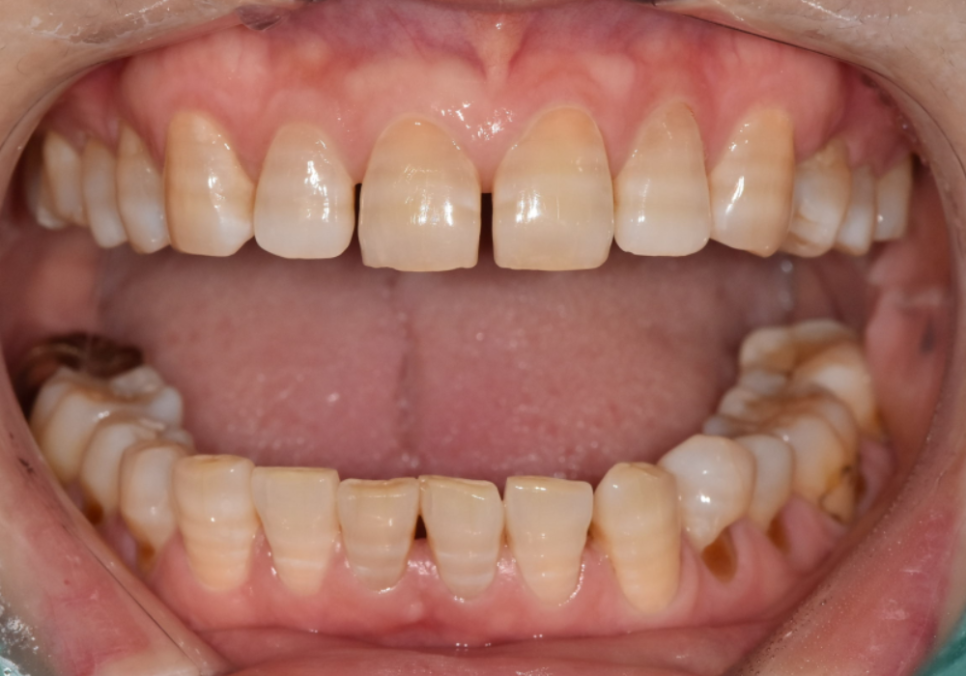

얼마 전에 내원하신 한 환자분이 특히 기억에 남습니다.

앞니가 벌어져 있고,

갈색 가로줄이 선명하게 보여서 웃을 때마다

입을 가리게 된다고 하셨습니다.

250220

자세히 보니 전형적인 항생제 변색이었습니다.

앞에서 말씀드린 것처럼 항생제 변색은

치아 내부 깊숙이 색소가 침착되어 있어서

치아미백효과를 거의 기대하기 어렵습니다.